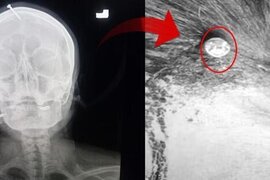

ŞOK HADİSƏ: Oğlu olsun deyə başına mismar vurdular - FOTO

Pakistanda hamilə qadın başında 5 sm uzunluğunda yara ilə xəstəxanaya yerləşdirilib. Əvvəlcə qəza kimi görünən hadisənin əsl səbəbi hətta həkimləri belə, şoka salıb. xarici mətbuata istinadən xəbər verir ki, 3 qızı olan ana, bətnindəki körpənin də qız olduğunu öyrəndikdən sonra ərinin ondan ayrılma